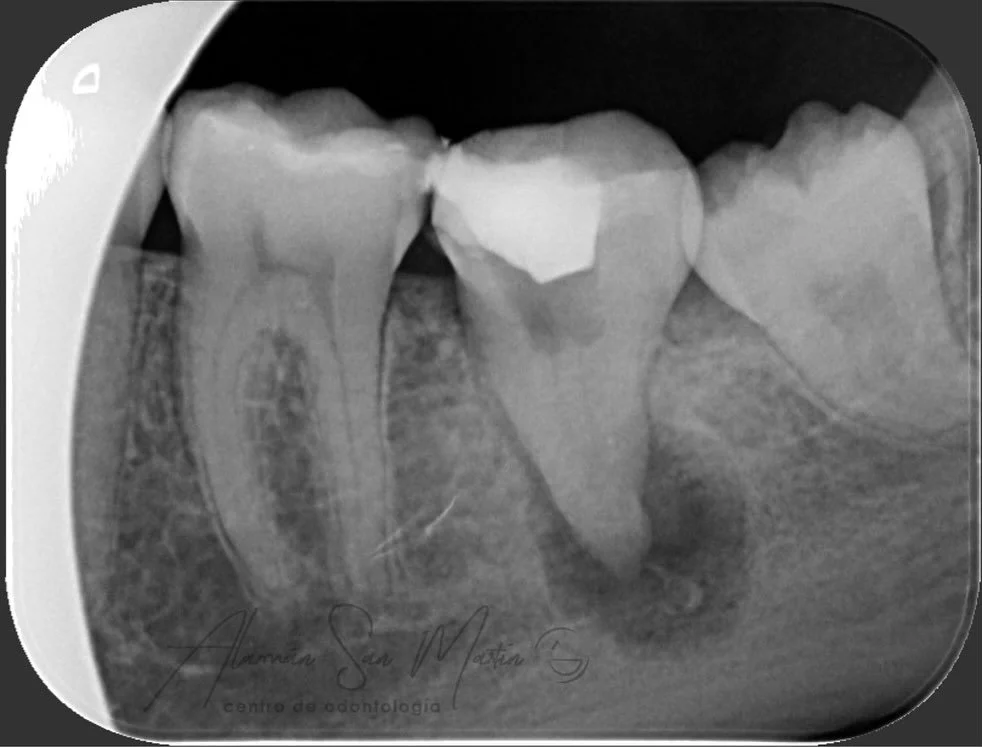

La Endodoncia consigue eliminar el nervio de los dientes con infección por caries o por algún traumatismo, y rellenarlo con material biocompatible, conservando el diente sin tener que extraerlo.

En nuestra clínica se realizan endodoncias por un Especialista En Endodoncia tratando desde casos sencillos a casos complejos de retratamientos o fracasos en endodoncias antiguas.

Utilizamos técnicas avanzadas de diagnóstico en endodoncia como la Radiovisiografía Digital, el Localizador de Ápice y Técnicas Rotatorias de instrumentación de los conductos radiculares, utilizando el microscopio en los pacientes que lo requieren.